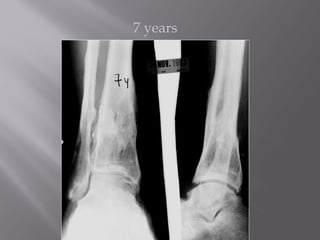

1986 - 24 yo Male

7 years

 Works light labor

 Prefers high top boots

 Occasional pain

 Ankle score 80